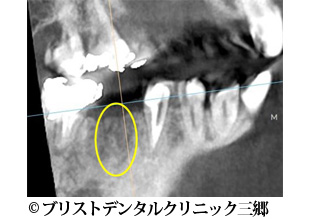

【症例3】インプラント

- 治療前

- 治療後

- 治療名

- インプラント

- 費用

- 450,000円(税込)

- 期間

- 9ヶ月

- 通院頻度

- 約2週間ごと

- 性別・年齢

- 女性 50代

治療内容

-

患者様の症状

右下奥歯が腫れてきて痛みがあり食べれないとのことで当クリニックに来院されました。

レントゲン上で右下の6番目の根の先端に大きい影が見られます。 -

治療法

まず被せ物を外し根の治療を行ったのですが歯根破折が確認できたため抜歯を行いインプラントにて噛み合わせを回復することにしました。

抜歯後半年経ってから骨が回復してくるのを待ちました。 -

治療結果

色合い等大変、満足されていました。また何でも噛めるそうです。

※治療結果は患者様によって個人差があります。

治療を行う上での注意点 (リスク・副作用)

歯磨き不足や定期検診に来られなかったりするとインプラント周囲炎になる可能性がある。

長期による経年劣化により被せ物を交換しなければならない場合がある。